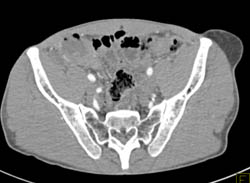

Symphysis Fracture With Bladder Laceration and Contrast Extravasation